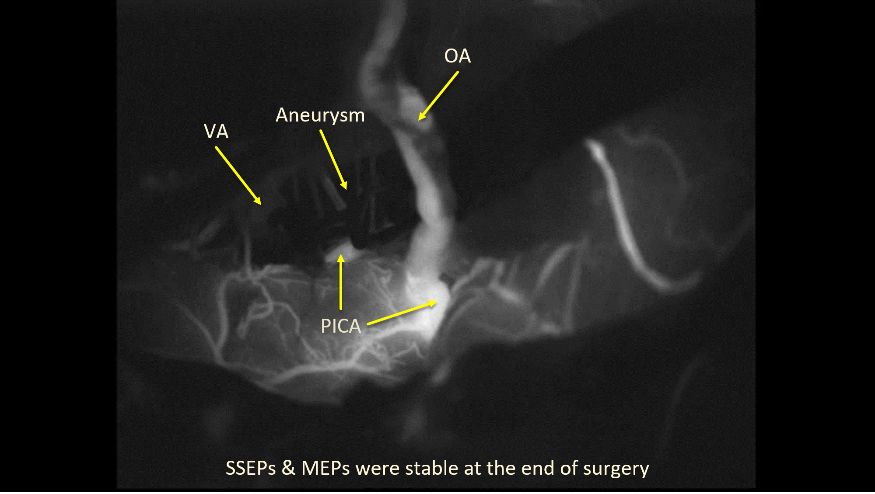

6. 复查吲哚菁绿(ICG)造影明确动脉瘤已闭塞,PICA近端有来自搭桥血管的反流。

7. 术中造影证实动脉瘤不再显影,桥血管通畅。